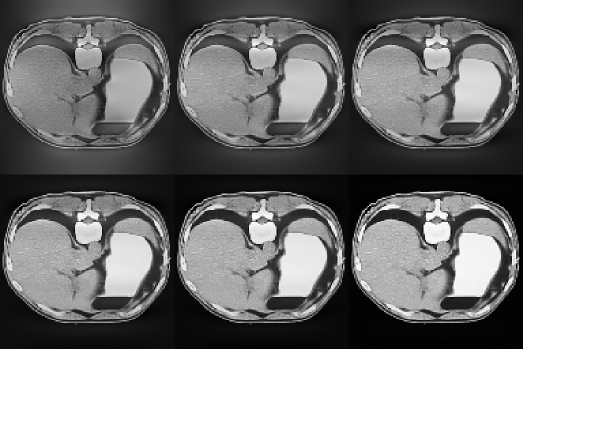

We use in all the numerical experiments with the alternating Bregman algorithm. In our first experiment we choose the almost two-to-one boundary voltage . The results obtained by applying the split Bregman algorithm with iterations are shown in Figure 2. A larger image of the conductivity reconstructed using the alternating split Bregman algorithm with is shown in Figure 3. This image may be compared with the original image in Figure 1.